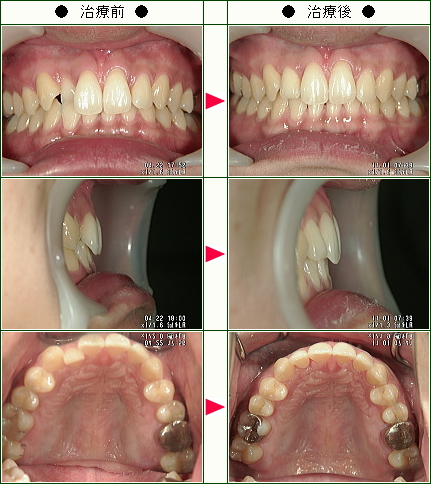

☆歯のデコボコ矯正症例(C・N様 26歳 女性)

結婚式までに綺麗な歯並びにしたくて治療を開始しました。

歯を抜かずに済むということ、短期間で終わるということ、前歯2本だけを治したいという私の希望にぴったりだったのでこの歯科に決めました。

歯を削るのが1番痛そうで不安でしたが、思っていたより痛くなくてよかったです。

毎回、わかりやすく説明をしてから治療を始めてくれるので、安心してまかせる事ができました。

仕上がりも、とても満足しています。

待合室でも、全く待たされることがなく、時間通りに治療が受けられるのも素晴らしいと思います。

家から2時間と少し遠いのですが、この歯科を選んで本当に良かったです。